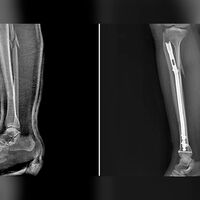

Пациентке диагностировали оскольчатый перелом костей голени, большой берцовой и малой берцовой костей. Травматологи под анестезией осуществили сращивание костей, закрепив их штифтом и винтами.

«Такой способ позволяет уйти от привычного гипса и исключить риск вторичного смещения, а также последствий в виде тромбоза, остеопороза, артроза», — пояснили медики.

Женщина смогла наступать на поврежденную ногу уже в первый день после операции. Через год пациентке предстоит еще одно вмешательство, на котором врачи удалят все металлические конструкции из ее ноги.